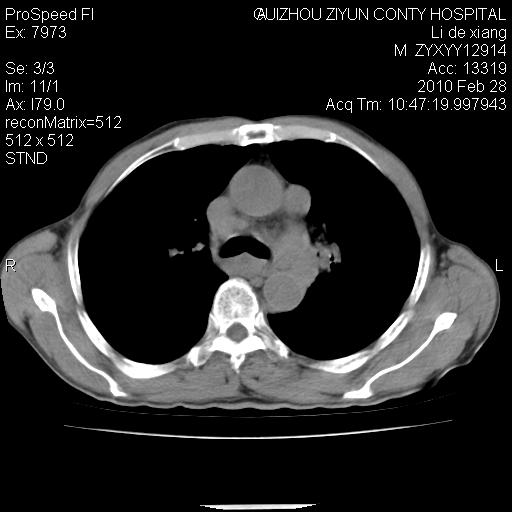

标题: CT24776:男 71Y 咳嗽咳痰胸痛两月,伴声音嘶哑。 [打印本页]

标题: CT24776:男 71Y 咳嗽咳痰胸痛两月,伴声音嘶哑。

左侧中央型肺癌伴左肺上叶阻塞性肺炎及节段性不张可能性大,建议纤支镜检查!

左侧中央型肺癌伴左肺上叶阻塞性肺炎及节段性不张可能性大,建议纤支镜检查!纵隔淋巴结转移.

左侧中央型肺癌伴左肺上叶阻塞性肺炎及纵隔淋巴结转移。

左肺门部肿块,伴左上肺斑块影,周边模糊,支持左肺中央型肺癌伴节段性不张及阻塞性肺炎,结合支气管镜检查。

左上叶支气管狭窄,阻塞性病变,肺门肿块,纵隔及肺门淋巴结增大,中央性肺癌

左肺中央型肺癌并阻塞性改变、纵膈 淋巴结转移